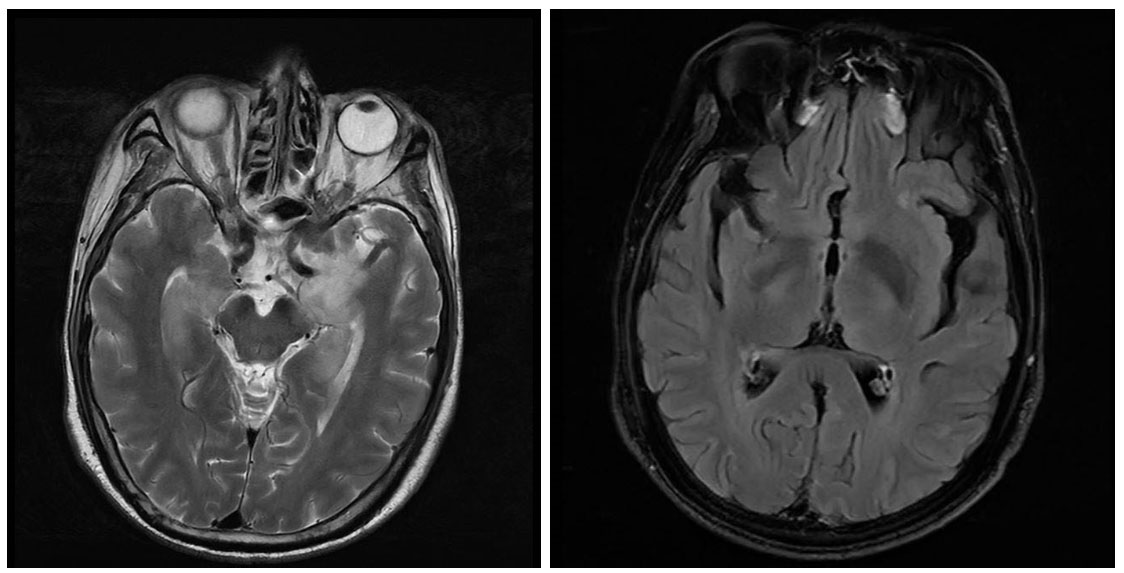

A为平扫MRI,B为增强MRI 图 3 头颅磁共振影像

入院后予以丙种球蛋白25 g qd(连用5 d)、甲强龙500 mg qd起降阶梯治疗(每3 d减半量); 同时辅以左乙拉西坦片0.5 mg q12 h鼻饲、苯巴比妥钠注射液0.1 g q8 h肌肉注射抗癫痫及其他营养对症处理。后患者病情逐渐稳定转入神经内科专科住院。经抗自免脑治疗后患者心律失常逐渐好转,予以摘除临时起搏器,并进一步行颅脑MRI及增强MRI检查,颅脑MRI(2021-11-10)提示:两侧额顶叶、左侧颞叶皮层下和两侧半卵圆中心见多发斑点状T1WI低、T2WI高信号,T2 Flair高信号,脑室脑沟脑池未见明显异常,中线结构居中。颅脑增强MRI提示:两侧颞叶、岛叶、额叶多发片状T2WI高信号影,T2 Flair高信号,DWI呈稍高信号,以额叶为主,两侧额顶颞叶、脑室周围、半卵圆区、基底节区多发点片状长T2高信号,黑水像高信号,脑室脑沟脑池未见异常,中线居中。两侧颞叶、岛叶及额叶多发病灶,考虑脑炎:两侧额叶颞叶、脑室周围、半卵圆区、基底节区多发缺血灶(图 3),癫痫治疗方案基本同上。1月后患者转入绍兴市上虞区人民医院行康复治疗,后患者逐渐恢复生活自理能力。半年后(2022-04)随访,患者于浙大一附院诊断为小细胞肺癌(晚期),目前行中药、化疗治疗。